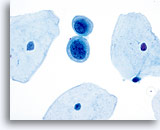

对于 ThinPrep® 涂片检测,HSIL 的诊断标准如下: 单个细胞(HSIL 最重要的标准)是不对称三维胞核结构异型的表现。为掌握 HSIL 诊断,必须对此概念有明确的理解。不良胞核的结构将发生异型变化;对于这些胞核而言,只有对单个细胞的焦距进行上下控制,才可对这些胞核做出彻底的诊断。此概念是最难以在书本图片(二维页面)上展示的;然而,这却是最为重要的。

试想想对一个微缩的花椰菜、握紧的拳头、棒球或扁桃腺的焦距进行上下对焦。葡萄干的表面看起来像什么?正常胞核的形状相对较圆或呈椭圆形,并且其表面也是平滑的。不良细胞将具有凸起、凹陷、褶皱、裂纹和奇怪的隆起。这些非常明显的异型性是异生性(特别是 HSIL)的基本特征;而由于传统的细胞涂片在固定和染色过程中会存在各种干扰物质,上述的细节往往会在传统的细胞涂片丢失 , 这样令传统涂片的诊断能力造成限制。

这些三维细胞结构的异型性可与简单的“不规则细胞核轮廓”区别开来;在 ThinPrep® 玻片上,这些将是良性细胞的一种特征表现。由于是二维的, 由于是二维的,当检查员在显微镜下上下对焦时,这些“褶皱”像裂缝或山脉般难以在胞核中心被追踪,这样会为无经验者做成相类似的假像。